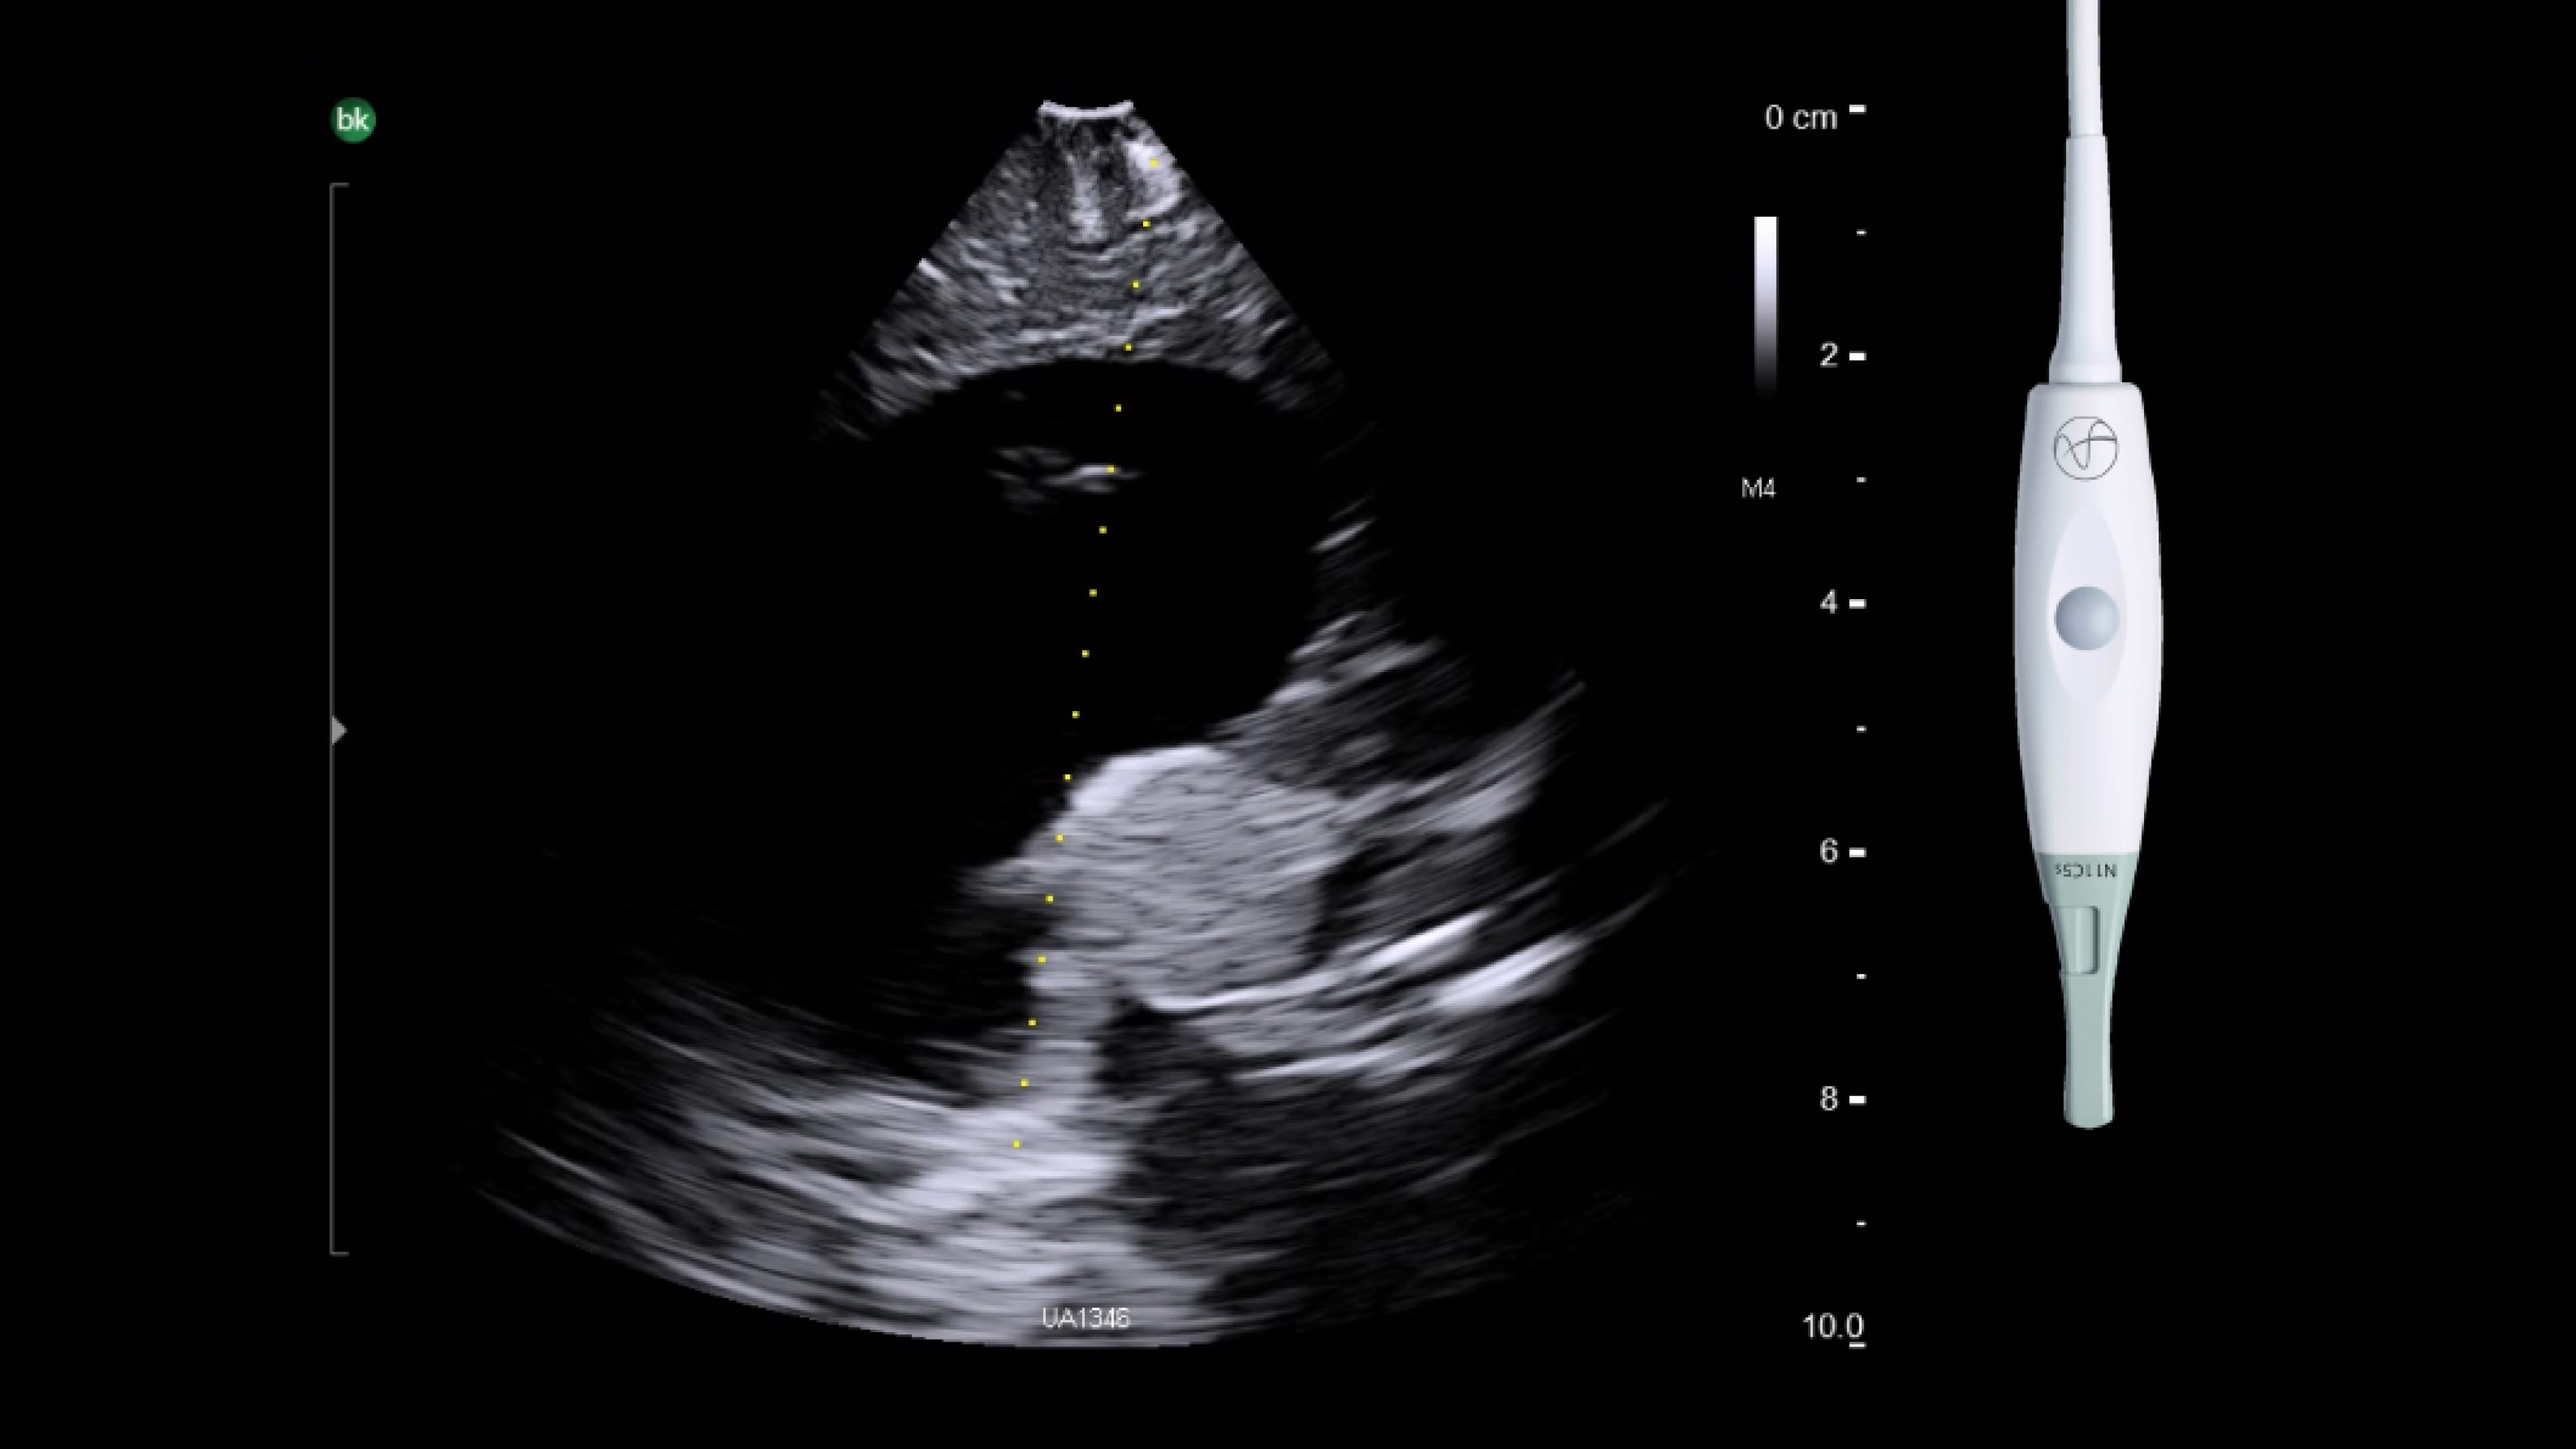

Skull base

Use intraoperative ultrasound during surgery to avoid injury by identifying blood vessels near the pituitary gland, access hard-to-reach areas and use through cranial endoports. With the bkPortfolio's smallest transducer monitor resection progress and assess for residual tumor.